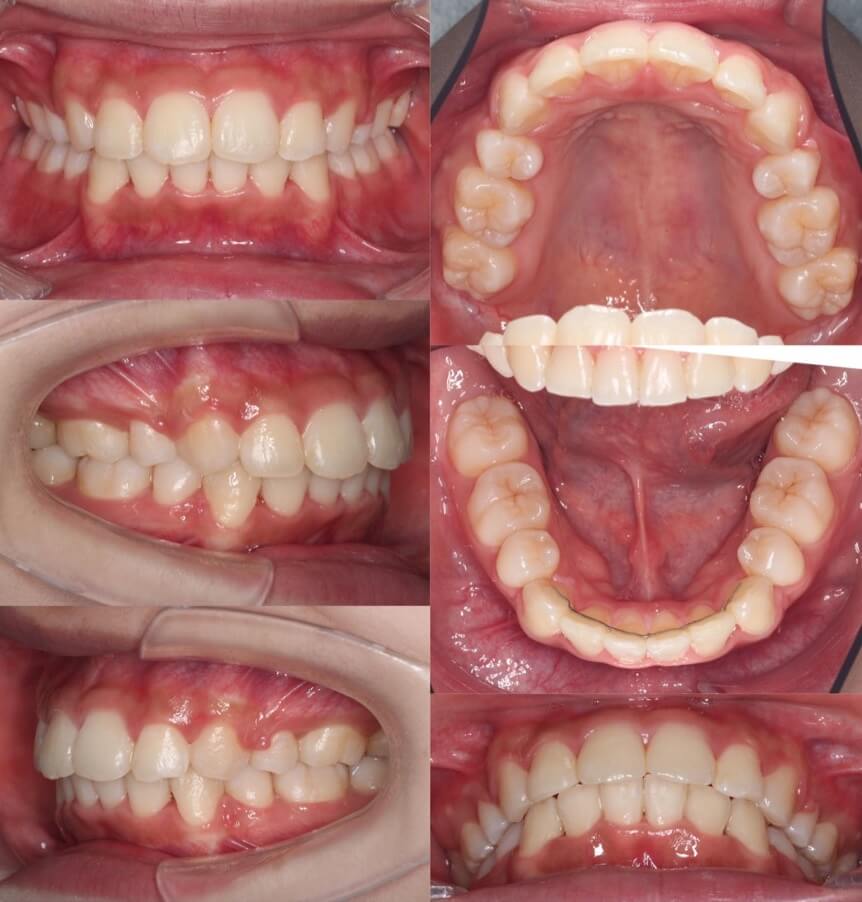

「あご先ができた」

大学生女性・唇側矯正・下あご後退型

<症例概要> 難易度:★★★☆☆

主訴:口元の突出

年齢・性別:大学生女性

住まい:千葉県八千代市

症状:下顎後退・上下顎前歯唇側傾斜

治療方針:抜歯空隙の閉鎖(最大固定)

治療装置:唇側矯正装置

固定:歯科矯正用アンカースクリュー(上顎頬側x2)

抜歯:上下第一小臼歯(計4本)

治療期間:2年2か月

リテーナー:上下プレートタイプ+フィックスタイプ

治療費用:968,000(税込)

代表的副作用:痛み・治療後の後戻り・歯根吸収・歯髄壊死・歯肉退縮

アンカースクリューを使用して、最大限に上下の前歯を後ろに引っ張りました。前歯を後ろに引く量は事前にレントゲン分析による横顔のシミュレーションを行って決定します。このように最大限後方移動させる場合は、アンカースクリューなどの固定源の追加が必要になります。治療後は、あごのしわがなくなり、口元がかなり引き締まりました。